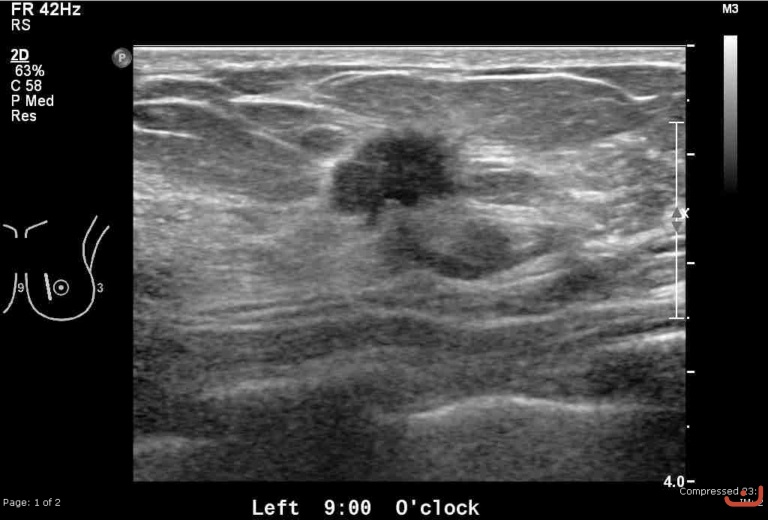

Malignant solid mass

Thursday, 30 April 2015

180.19 KB (768 x 520 px)